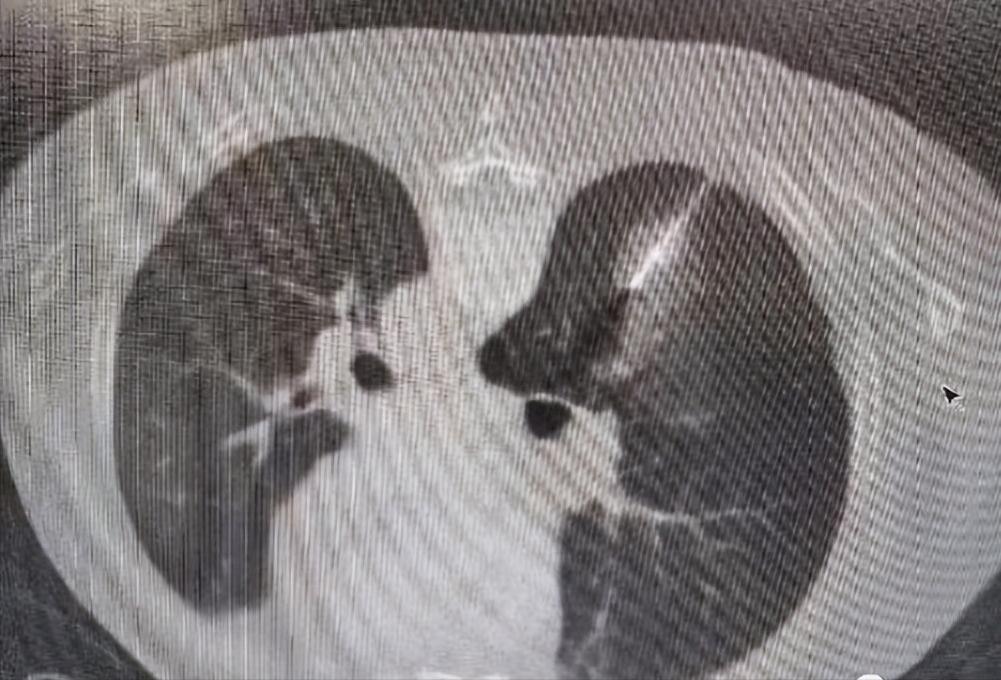

消融治疗中:

微波消融(MWA)一般采用915 MHz或2,450 MHz两种频率。在微波电磁场的作用下,肿瘤组织内的水分子、蛋白质分子等极性分子产生极高速振动,造成分子之间的相互碰撞、相互摩擦,在短时间内产生高达60℃-150℃的高温,从而导致细胞凝固性坏死。由于辐射器将微波能集中在一定范围内,故而能有效地辐射到所需靶区。微波消融只会损伤局部设定范围内的细胞而不会破坏周围的组织,消融范围可控。

因此,本次手术方案中一次穿刺操作,既可以取得结节的病理结果,又可以消融结节,使患者在最小的创伤下得到最大的获益。